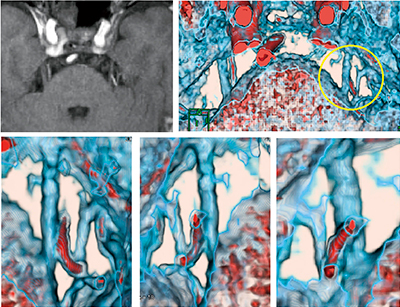

4.水頭症フェーズコントラストフュージョンイメージ

非交通性水頭症例における第三脳室底開窓術(EVT)の,手術前後での脳脊髄液のフローの確認に用いる。通常のフェーズコントラスト画像のシネ表示でも脳脊髄液のフローの確認はできるが,マグニチュード画像をカラー化してリフェーズ画像とフュージョンすることで,より明瞭にフローの存在部位や程度を確認することができる(図4)。

図4 水頭症フェーズコントラストフュージョンイメージ

第三脳室底開窓術後のフローなどをカラー化してシネ表示する。